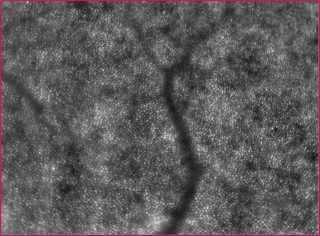

The rtx1 is designed to image the retina at the cellular scale, enabling clinicians to observe the microvascular structures that are frequently affected by vision-degrading diseases.

During an examination the camera images retinal areas in a field of 4 degrees x 4 degrees, capturing enough of the vascular pattern to allow accurate registration of the adaptive optics image with other diagnostic techniques, such as fundus imaging or OCT.

The field is illuminated by a 850 nm LED, based on a 32 x 32 microlens optoelectronic sensor and a large-stroke 52-actuator electromagnetic deformable mirror. While the AO system is compensating for the eye’s optical defects, the instrument is focused at the retina's cone photoreceptor layer, and a series of 40 raw images acquired by exposing the retina to 9 ms near-infrared flashes, fast enough to avoid the blurring of the image due to natural eye drift. An image with enhanced contrast is computed by registering and averaging raw images using classical algorithms.